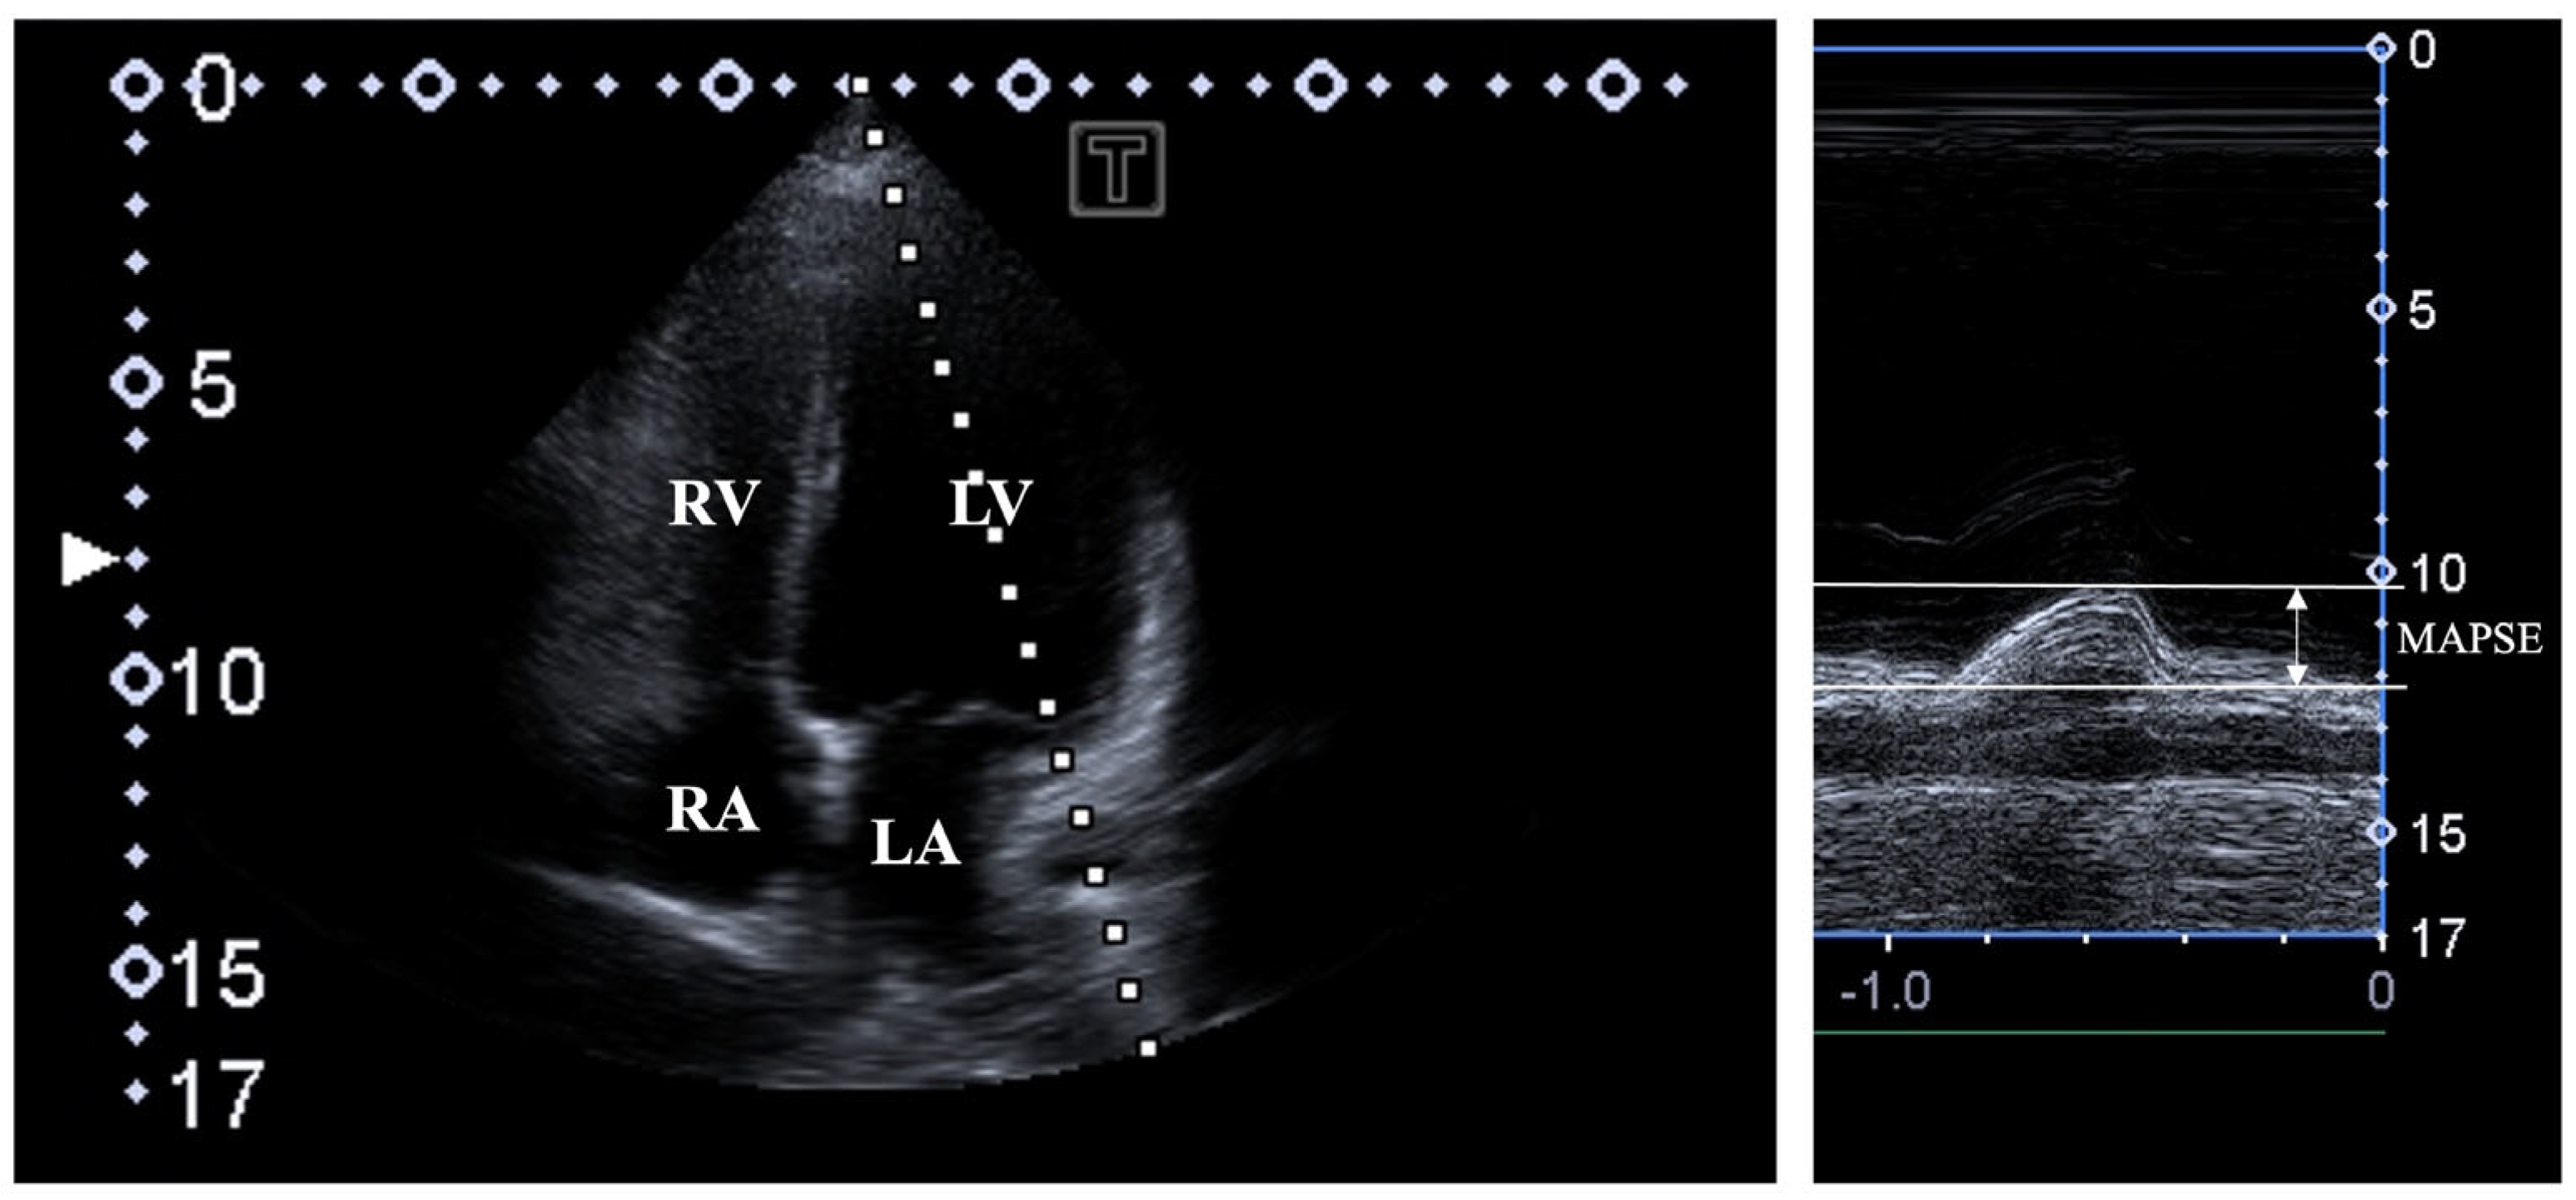

2. Materials and Methods

3. Results